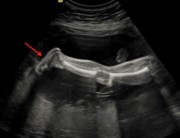

این تصویر پای جنین را در هفته 21 بارداری نشان میدهد. فلش قرمز اشاره به پای جنین دارد.

این تصویر نشان دهنده پای جنین در هفته 21 است. می توانید شست (پیکان قرمز)، انگشتان پا و پاشنه را به وضوح تشخیص دهید.